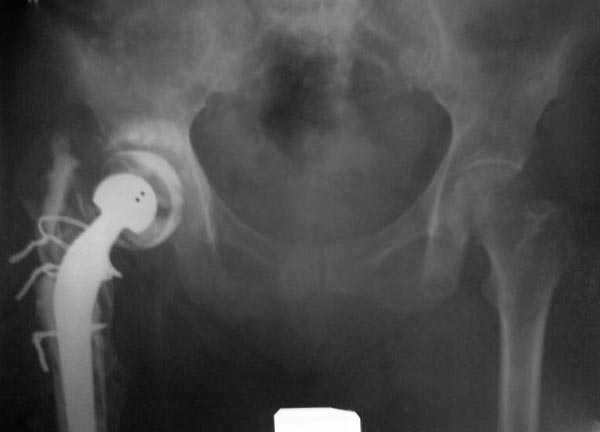

Из предложенных вариантов быстрейший результат можно ожидать после поэтапного эндопротезирования.

"Антибиотико-цементные" спейсеры после купирования

инфекции уже после первого этапа позволяют больным

передвигаться самостоятельно, иногда нагружая конечность годами.

Как-то показывал случай после осложненного тотального эндопротеза, сперва из-за отсутствия экономических возможности, а затем привыкшая к своей участи вот уже более 8 лет ходит на временном "протезе-спейсере".

Полость вертлужной впадины и проксимальное бедро были заполнены custom made временным протезом из цемента.